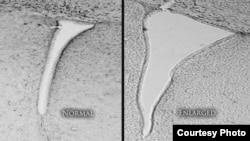

FILE - A mouse brain that was exposed to polluted air shows an enlarged lateral ventricle (right) compared with a mouse whose air was clean and filtered. Enlarged lateral ventricles are associated in humans with autism and schizophrenia. (University of Rochester Medical Center)